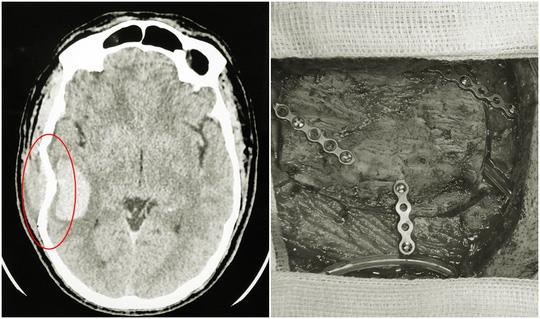

Kết quả thăm khám, chụp cắt lớp vi tính cho thấy bệnh nhân B. bị chấn thương sọ não: Vỡ xương sọ, rách màng não, chảy máu não.... Sau khi hội chẩn, các bác sĩ đã quyết định mổ cấp cứu ngay trong đêm để xử trí kịp thời tình trạng chấn thương, lấy máu tụ trong não và phần não dập, tạo hình lại hộp sọ và màng não cho người bệnh.

| Hình ảnh sọ não bị lún vỡ được các bác sĩ phẫu thuật nẹp vít tạo hình lại hộp sọ. |